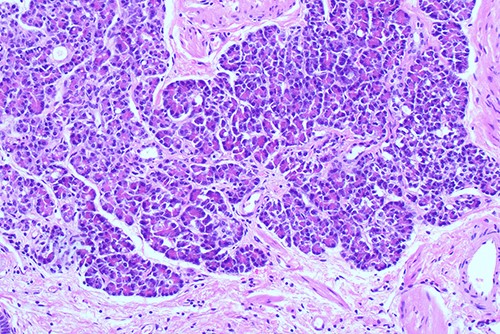

She proceeded to an elective laparoscopic cholecystectomy. At the time of her procedure, she was found to have features suggestive of chronic cholecystitis with peritoneal adhesions. Her procedure was straightforward and intraoperative cholangiogram showed a spiral cystic duct with the trifurcation of intrahepatic ducts. Her common bile duct appeared mildly dilated however tapered at the lower end and showed filling of the duodenum with no filling defects. The histology from the gallbladder showed variable fibromuscular thickening of the wall with intramural cystic Rokitansky-Aschoff sinuses, but no significant inflammation. Focal ectopic pancreatic acinar tissue (1 mm) within the gallbladder was found (Figs 1–3). There was no evidence of intestinal metaplasia, dysplasia or malignancy.

Histological examination ×100 showing ectopic tissue consisting of pancreatic acini and small ducts. No islets are seen.